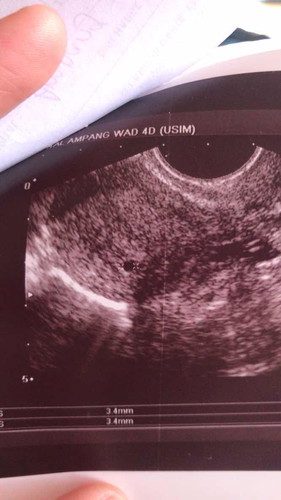

semalam pergi hospital, doctor cakap kandungan saya dah takde. rahim dah kosong. dengan hati yang terbuka saya terpaksa terima walaupun dah dua tahun menanti. tapi nak buat macam mana dah Allah yang tentukan kan? ? tapi harini saya bleeding banyak sangat. pergilah balik hospital kononnya nak cuci lah. tapi doctor pakar check kantung saya ada & kantung makin membesar. mengamuk doctor pakar tu dekat doctor satu lagi. nasib baik tak cuci dulu. tapi saya taktahu pendarahan ni kenapa, kakak ipar saya kata mungkin bunting pelanduk. ada sesiapa pernah kena ke bunting pelanduk? bahaya ke?